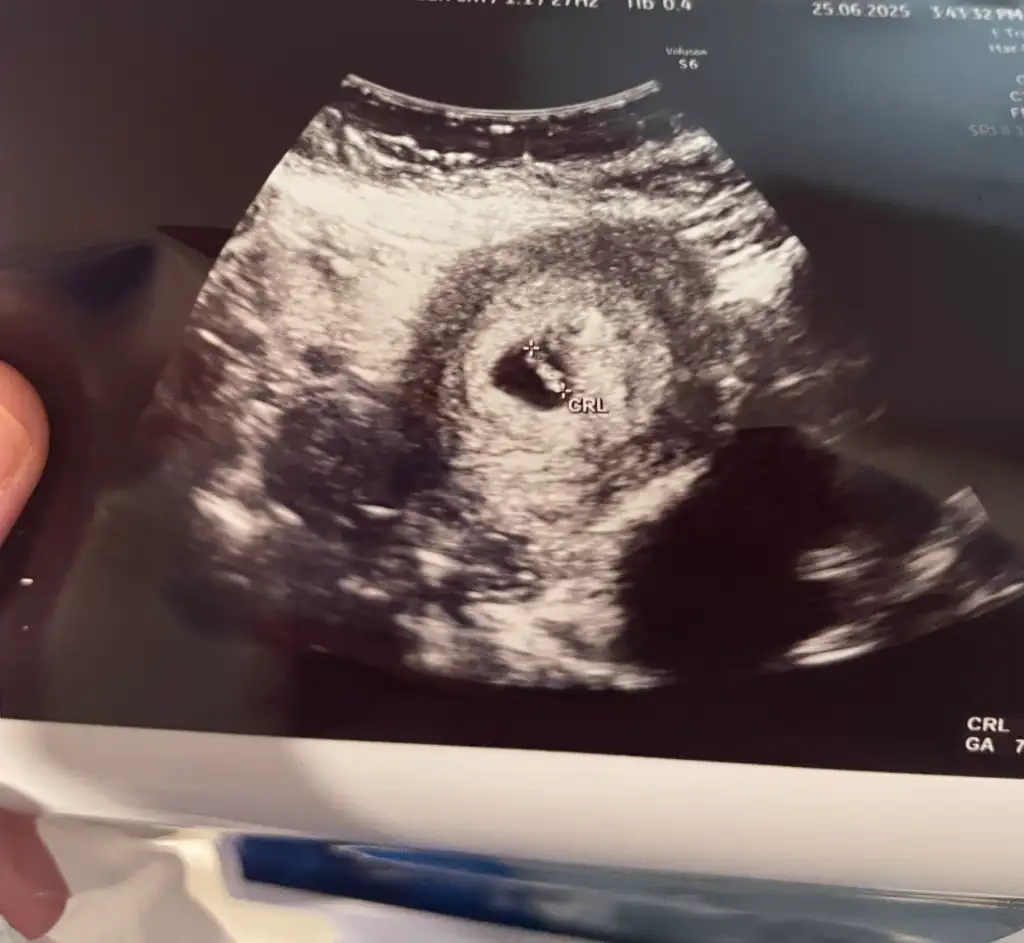

Maşallah ne kadar büyümüş bende 10.haftama gireceğim böyle mi görünecek yaa çok duygulandimKızlar benim randevum cumartesi günüydü ben dayanamadım biraz karnım ağrıyor diye bu sabah gittim.

Ultrasonda 10+1 çıktı.

Bebiş bayağı büyümüş ultrason fotoğrafını bırakıyorum size.